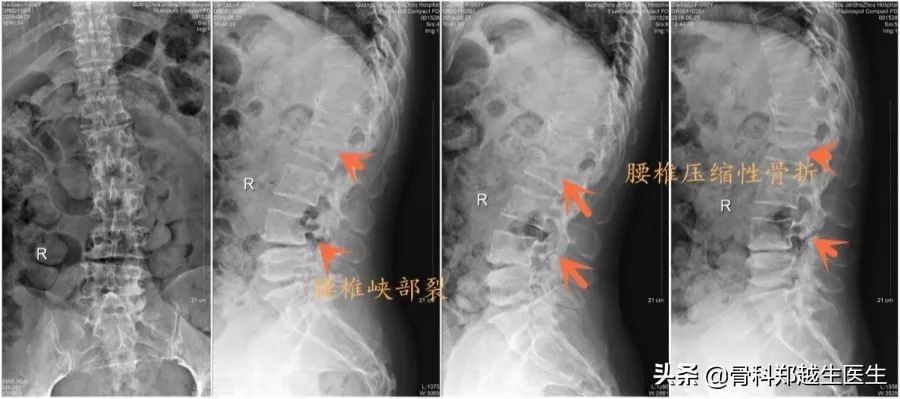

患者,蔡某,女,55岁,因“腰腿痛2年,四肢麻木2月”就诊,患者在当地医院就诊,行腰椎CT检查,诊断为腰椎间盘突出症,在中医门诊行推拿按摩治疗,开始治疗时腰背痛缓解,医生交代需要多次治疗,在有一次治疗时患者突然出现腰部疼痛加重,翻身疼痛加剧,不能坐起和站立,经腰椎X线检查,提示腰椎压缩性骨折。随后转至我科治疗。

入院后体查:肚脐以下皮肤浅感觉减退,腰椎后凸畸形,L2椎体压痛、叩痛(+),L4-L5棘突间触及台阶感,直腿抬高试验(-),股神经牵拉试验(-),双下肢膝腱、跟腱反射正常,病理征(-)。

影像学检查提示:L2椎体压缩性骨折,L4椎体峡部裂并椎体滑移,T1椎体层面椎管内肿瘤。